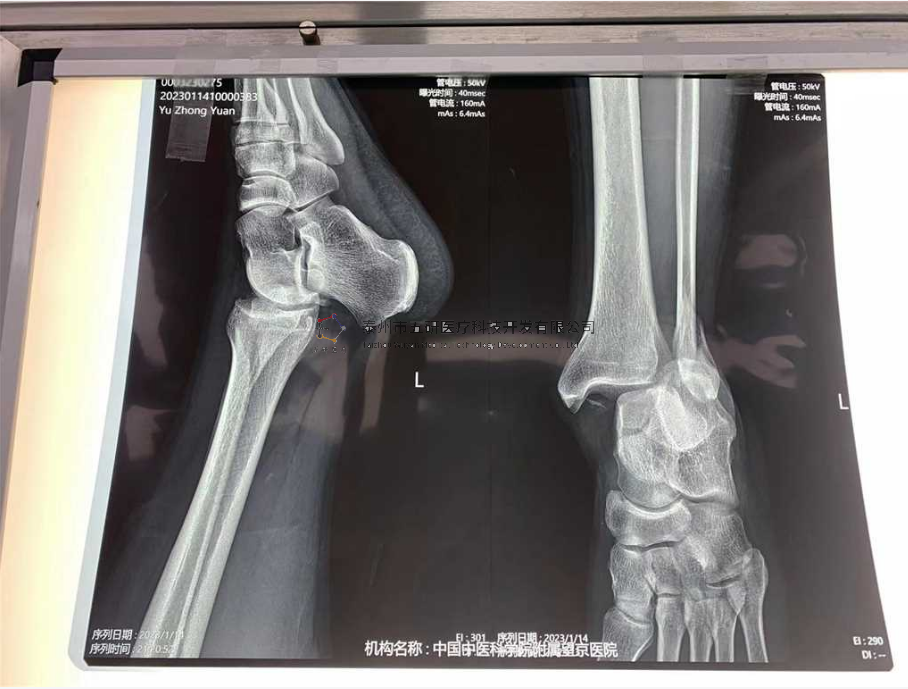

// 踝關(guān)節(jié)

本病例由中國(guó)中醫(yī)科學(xué)院望京醫(yī)院骨關(guān)二提供(術(shù)者:支架主任蔣主任)

【基本資料】患者,男,41歲

本病例踝關(guān)節(jié)骨折。手術(shù)名稱:左踝關(guān)節(jié)骨折外固定支架手術(shù)

【治療前影像】